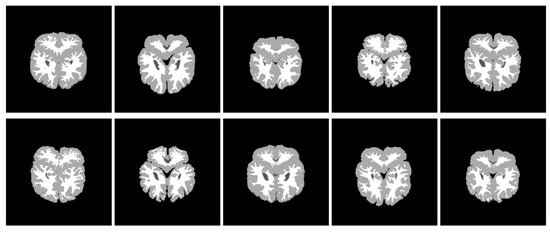

In this section, we show the performance of thresholding segmentation with the convex combination of pseudo grouping functions and the convex combination of grouping functions on 10 T1 weighted MRI images (see Figure 11). The MR cerebrum information as well as hand-operated segmentations originated from the morphometric analysis center of Massachusetts General Hospital. We evaluated the quality of excision by comparing with the ideal manually segmented images obtained on the same web page (see Figure 12). The purpose of this image segmentation was to divide each pixel in the cerebrum into two kinds—gray matter and white matter. In fact, it is a part of brain region volume analysis, which plays a great role in assessing the development of illness, for instance, Alzheimer’s disease, epilepsy or schizophrenia ([39,40]).

Through the convex combination of the above grouping functions and pseudo grouping functions, the results of threshold segmentations of 10 graphs are as follows (see Figure 13 and Figure 14).

We show the experimental results through specific data. In Table 13, we reveal the threshold obtained from every picture as well as the percentage of good sorted picture elements. The second column presents the outcomes gained from the convex association of grouping functions, and the third column presents the outcomes gained from the convex association of PGFs. As we can see from the experiment, our method has higher accuracy, that is, the use of convex association of PGFs significantly improves the segmentation accuracy of each image.

Then, in contrast with Otsu’s algorithm ([41]), the thresholding method on the basis of pseudo grouping functions has greater advantages. In Table 14, we show the thresholds obtained by the two algorithms and the percentage of pixels with good classification. We can find that our method obtains the better results for each picture in the test case, hence it mends Otsu’s thresholding technique with regard to the group of pictures.